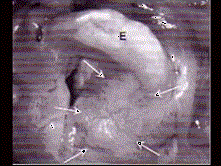

问题 男,60岁,因吞咽疼痛伴咽异物感一个月就诊。间接喉镜下检查发现会厌侧面轻度糜烂、不光滑、隆起,既往有吸烟史。 CT检查见下图,进一步的检查是 ( )

选项 A、放疗 B、活检送病理 C、密切观察 D、抗生素治疗 E、纤维喉镜检查以明确病变范围

答案 B